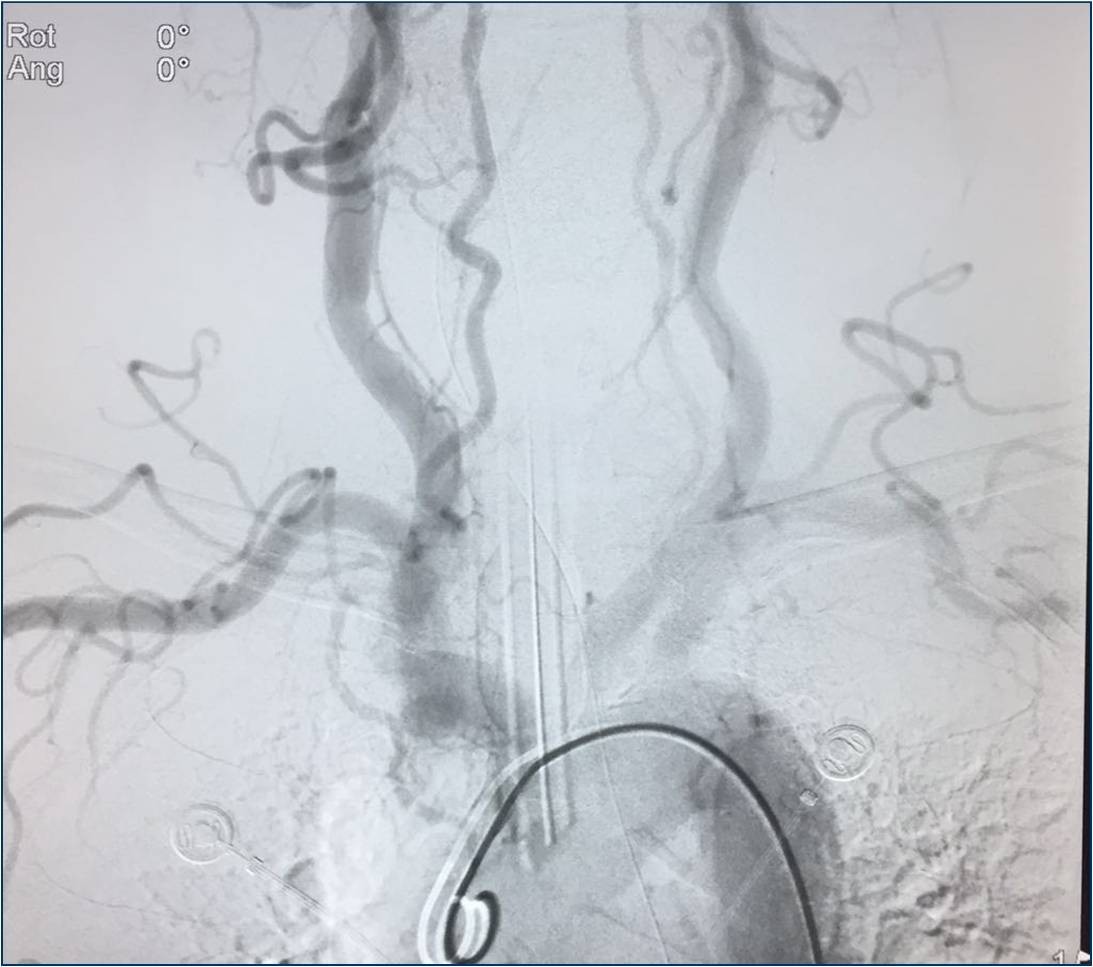

▼行造影明确动脉闭塞部位